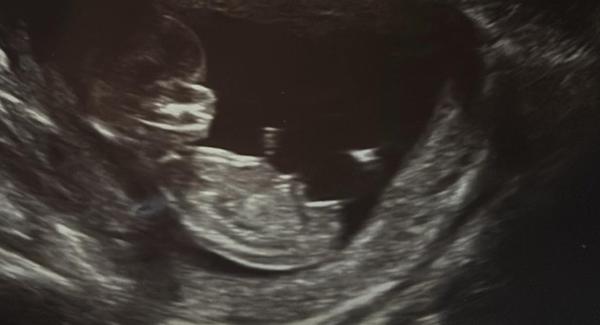

Určitě tě nemine 3D ultrazvuk.

@michaelka84 Ten narozený 1/2021 byl kluk 🙂 Z Utz v tom 13tt jsem si laicky tipovala holku, ale v 20tt už to bylo velmi jasné, ukazoval se dost 😀 V roce 2018 se nám narodila holka a tam jsem tedy nevěděla (doktoři neřekli do 34tt, chtěli úplatek), pořád jsem hloubala, zda to je kávové zrno či kulky 😀